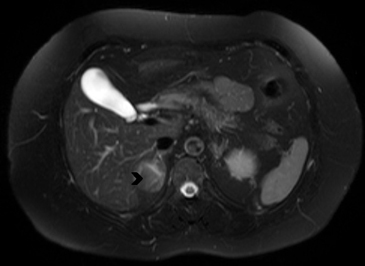

Figura 3. Glándula suprarrenal normal en resonancia magnética. (a) Cortes axial ponderado en T1 la señal de la glándula normal (flecha negra) es hipointensa respecto a la grasa retroperitoneal e isointensa respecto al parénquima hepático. (b) Cortes axial ponderado en T2 en que se muestra la glándula suprarrenal derecha (flecha blanca) y (c) corte coronal ponderado en T2 en que se muestra la glándula suprarrenal derecha (flecha blanca) y la glándula suprarrenal izquierda (flecha negra) con similares características de intendidad de señal. 3. Causas y prevalencia de las lesiones suprarrenales